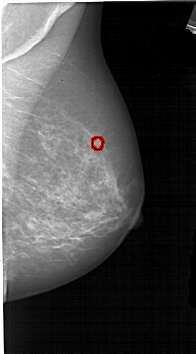

A_1894_1.RIGHT_MLO

FILE: A_1894_1.RIGHT_MLO.OVERLAY

TOTAL_ABNORMALITIES 1

ABNORMALITY 1

LESION_TYPE CALCIFICATION TYPE PLEOMORPHIC DISTRIBUTION CLUSTERED

ASSESSMENT 4

SUBTLETY 2

PATHOLOGY MALIGNANT

TOTAL_OUTLINES 1

BOUNDARY